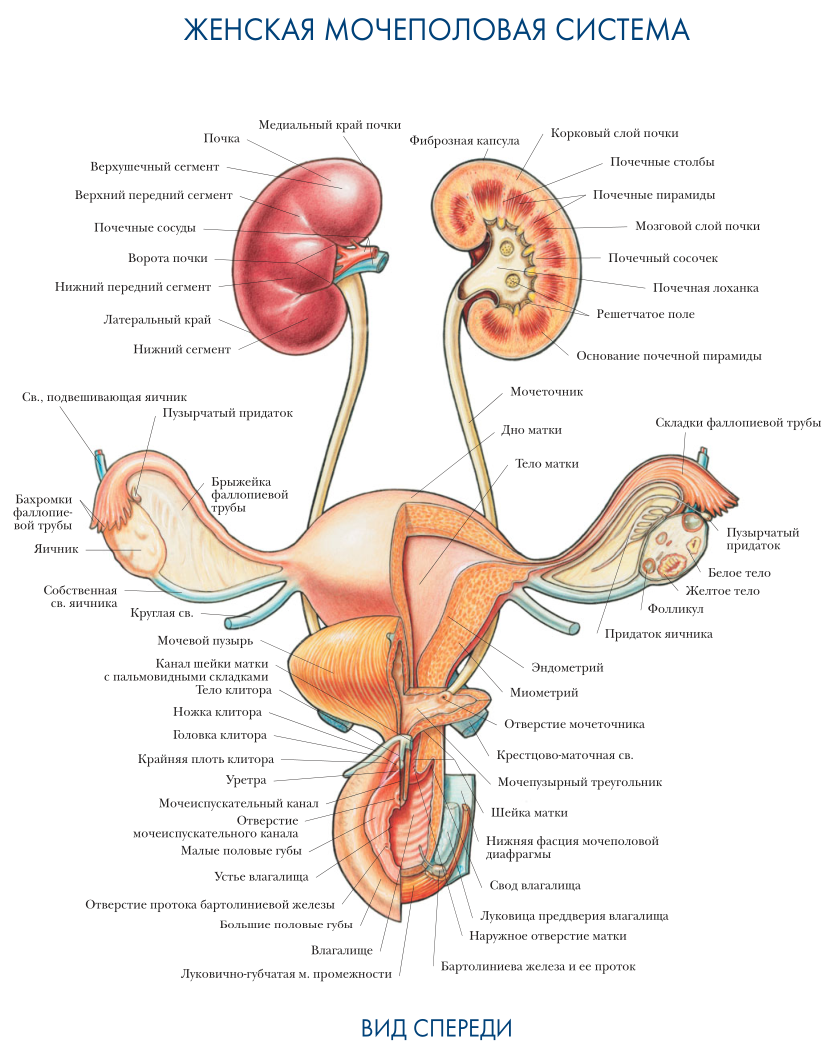

Физиология беременности: строение органов